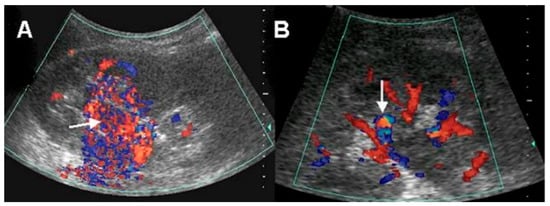

Six (46.2%) patients underwent renal duplex color Doppler US. All of these patients showed a high velocity of blood flow in the renal parenchyma and were correctly diagnosed as AVM. Of them, two (33.3%) patients showed vascular mass-like lesions, and four (66.7%) patients showed a vascular turbulence lesion. (Figure 1).

Figure 1. Doppler ultrasonographic findings: (A) conglomerated vascular structure (arrow) with blood-flow-rich area, (B) vascular turbulence (arrow).

The duplex color Doppler US in AVM demonstrates multidirectional, turbulent, and increased flow velocity, a mosaic pattern, and perivascular soft tissue color speckling [1,10]. Spectral analysis showed increased velocity and decreased resistance [1,11]. High-velocity blood flow with a diastolic component in the feeding artery and arterial pulsations in the draining vein is characteristic of arteriovenous shunting. Nagamura et al. revealed that color Doppler US in AVM clearly showed an area rich in blood flow with innumerable posterior color spots [12]. Several studies have suggested that duplex color Doppler US is useful in assessment of renal AVM including small cirsoid type and for the differential diagnosis of other mimicking disease entities [10,11,12,13]. Takebayashi et al. assessed color Doppler US in six patients with AVMs. In their study, AVMs were detected with focal areas of flow and as a mixing of lighter colors. They suggested that color Doppler US can be used for diagnosing and monitoring AVMs and could eliminate a considerable number of angiograms [10]. Donmez et al. suggested that duplex color Doppler US provides more information than gray-scale US for the diagnosis of renal AVM with cystic lesions showing the vascularization of the septa or the solid component of the cystic lesion [13]. Using duplex color Doppler US, small renal AVMs that are not visible by conventional US can be detected. We confirmed those findings in this study. In our results, patients who underwent renal duplex color Doppler US were all correctly diagnosed as AVM. Despite its invasiveness, arteriography is the gold standard for evaluating renal AVM. Taken together, we consider duplex color Doppler US as useful non-invasive diagnostic method for renal AVM, and it would be recommended in patients with no apparent cause of hematuria on conventional US or CT.